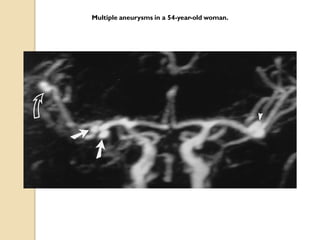

Multiple aneurysms in a 54-year-old woman.

Aneurysms  3D TOFis now accepted as a non-invasive screening tool for familial aneurysmal disease.  Sensitivity is greater for detecting aneurysms > 3mm (94%) than aneurysms < 3mm (38%). ( White et al 2000)  Overall inferior to DSA and misses aneurysm <3mm.(Adams et al 2000)  3D CE MRA is superior to TOF MRA .It is method of choice for evaluation of giant cerebral aneurysms.  CE MRA shows promise in the follow-up of treated intracranial aneurysms.

Multiple aneurysms ina 54-year-old woman.